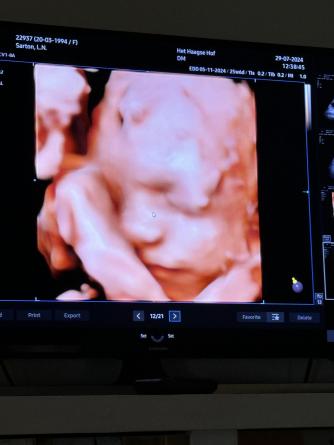

Week 20

Maandag 29 juli 2024